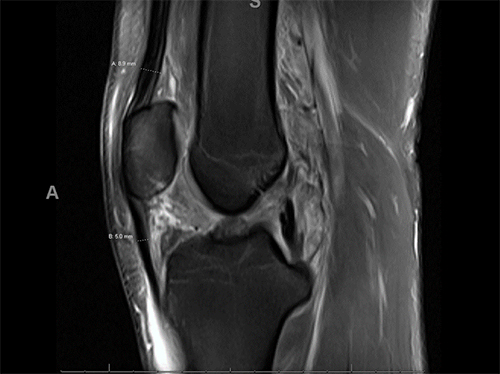

Figure 3 demonstrates the thickness of a quadriceps tendon compared to the patellar tendon on MRI.